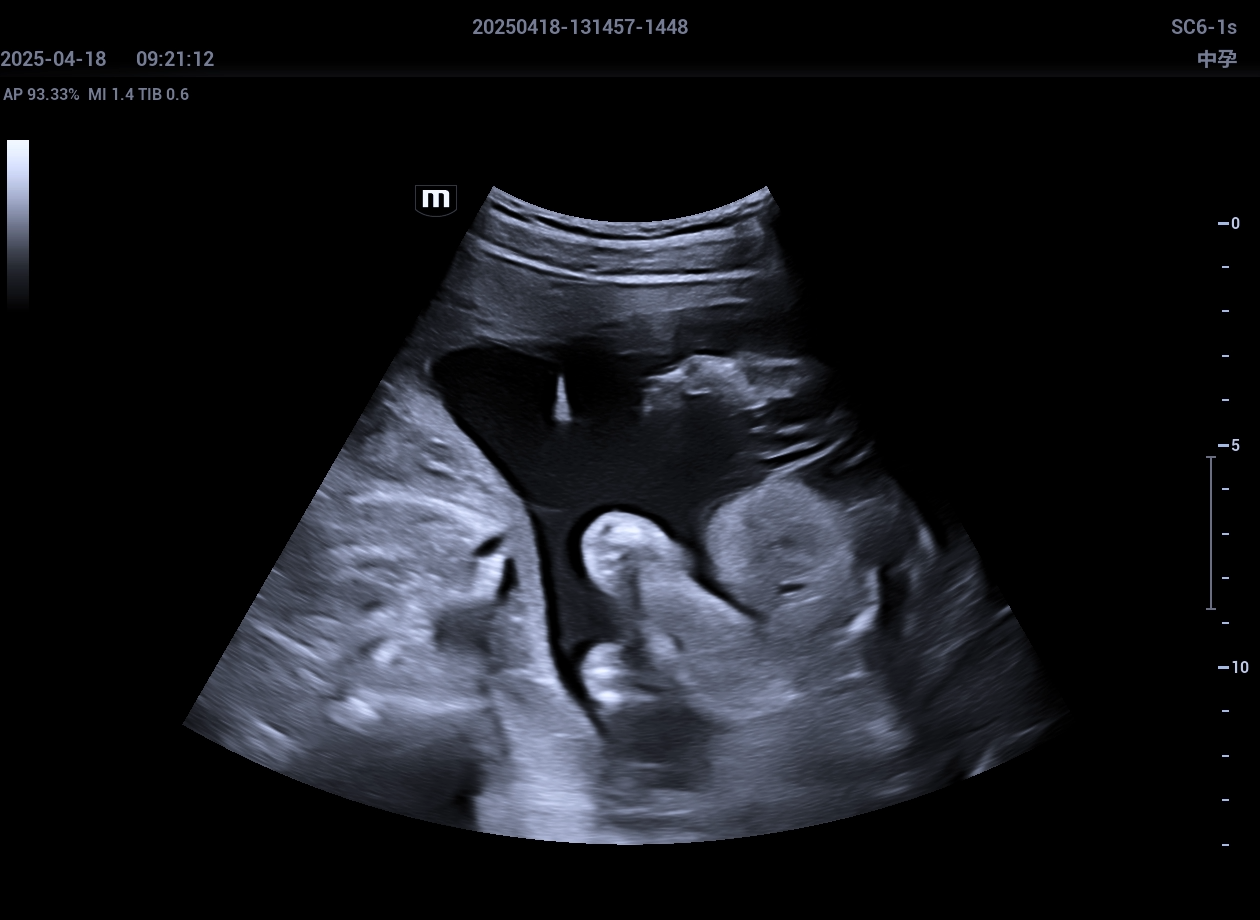

实例,超声引导羊水穿刺,胎盘绒毛膜穿刺,广西区妇幼保健院优生遗传科,2025年4月